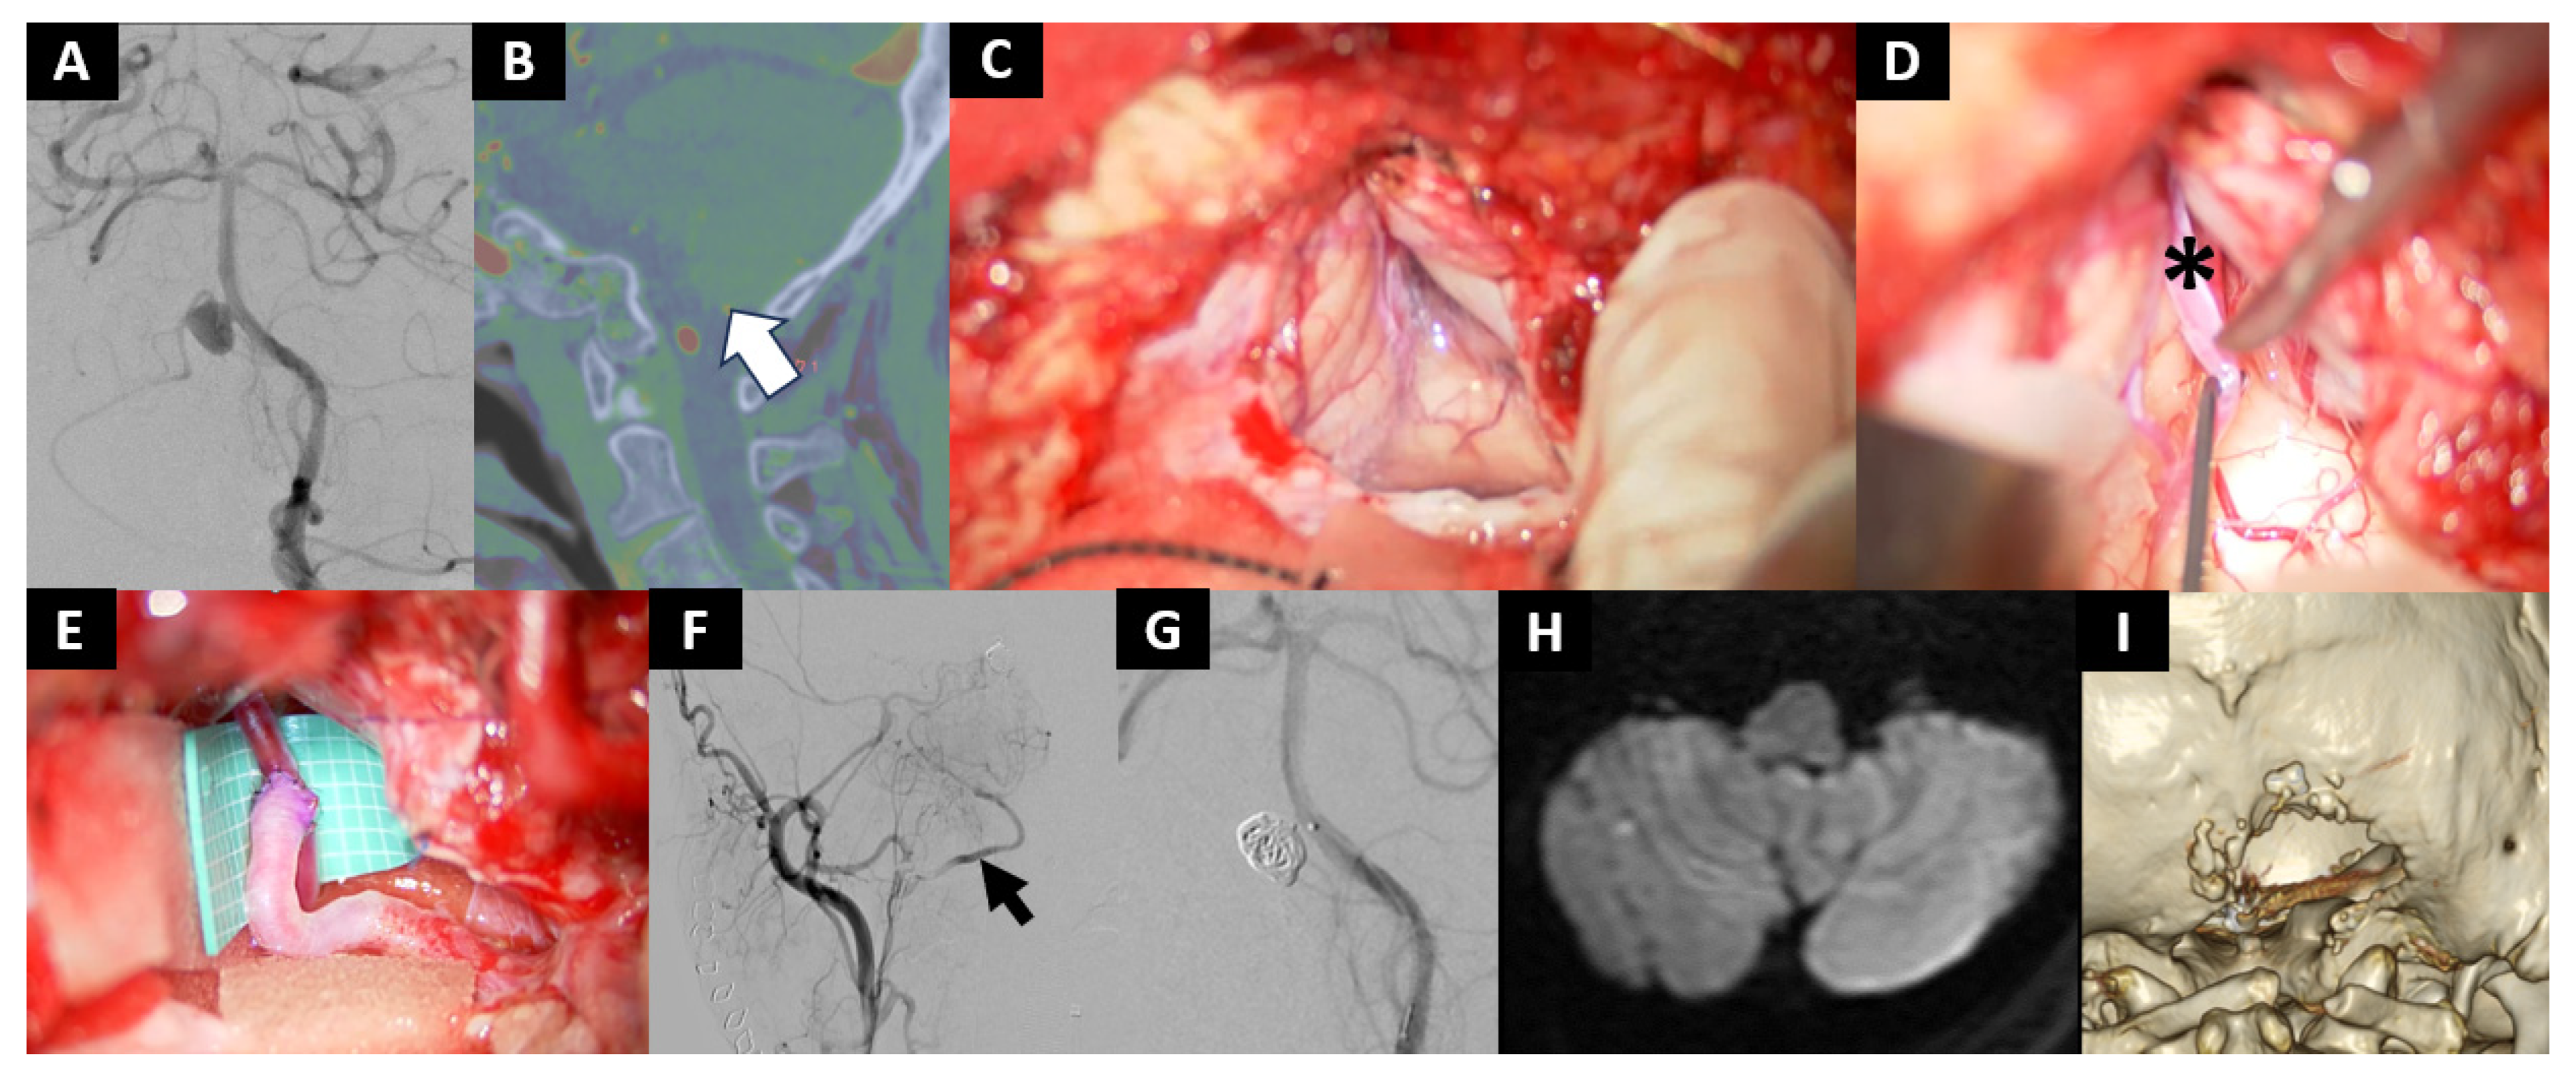

- Case No. 10

| 10 | 57 | F | saccular | VA-PICA | 3 mm | OA-PICA & trapping | None | - | - | - | moderate | 0 |